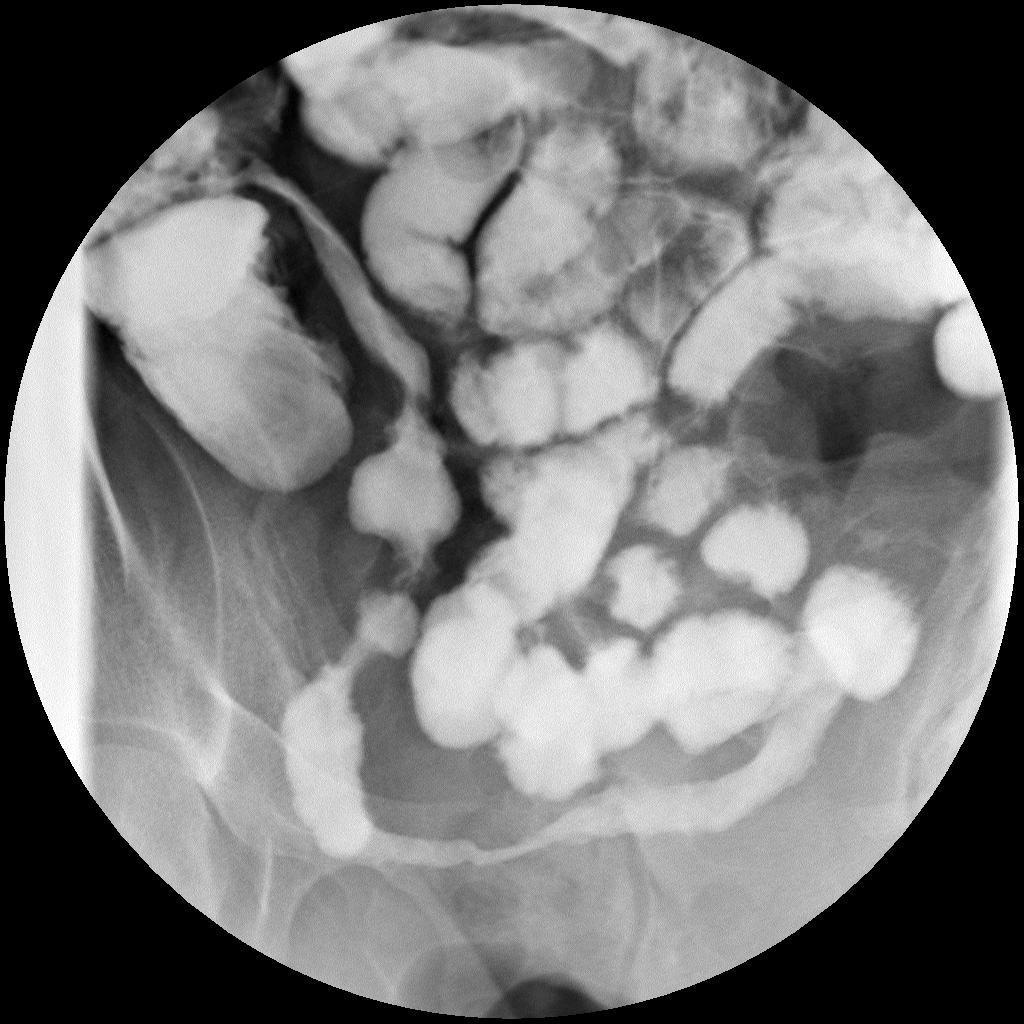

Barium enema of “lead pipe colon”

Loss of haustral marking characteristic of UC

Apple core colon

Characteristic of colorectal carcinoma

Cobblestone appearance of colon

characteristic of Crohns